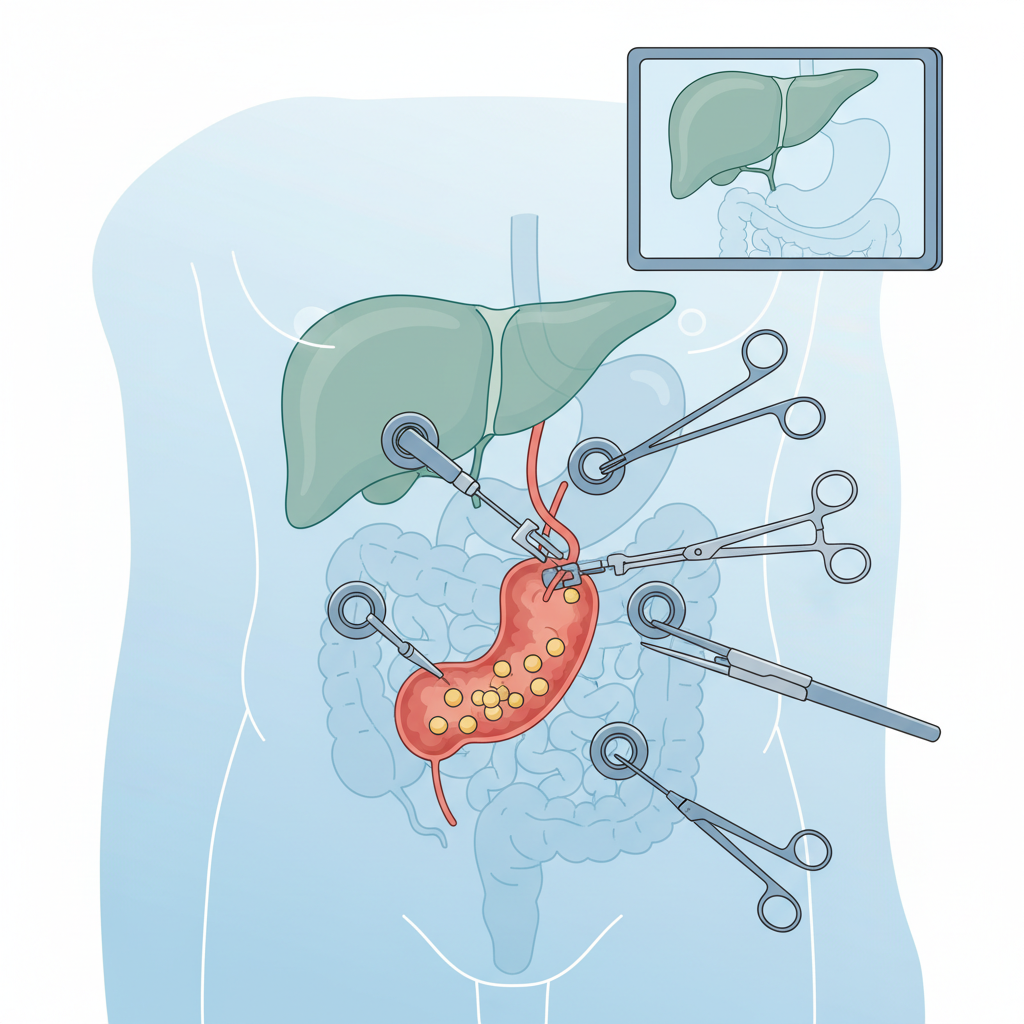

Tekrarlayan ağrı atakları olan, komplikasyon gelişen veya yüksek riskli hastalarda en sık önerilen yöntem laparoskopik kolesistektomi (kapalı safra kesesi ameliyatı)dir. Genel olarak:

Ameliyat sonrası süreç ve beslenme için ayrıca şu içeriği okuyabilirsiniz: Safra kesesi ameliyatı sonrası beslenme rehberi.